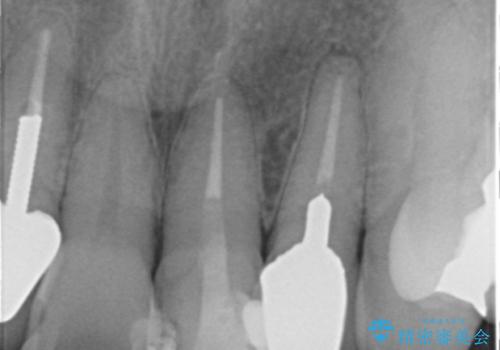

左上の前歯のみねじれが大きいため、歯の位置をひっこめたかぶせものにするために、神経の治療を行っています。

- 59.5万円 (オフィスホワイトニング 3万円、ジルコニアクラウン スタンダード 10万円×4本、仮歯 1万円×4本、精密根管治療(左上1)6万円×1本、ファイバーコア 2万円×1本)費用は治療当時の料金となります

両側の歯の神経の治療および土台のやり替えは行っていません。